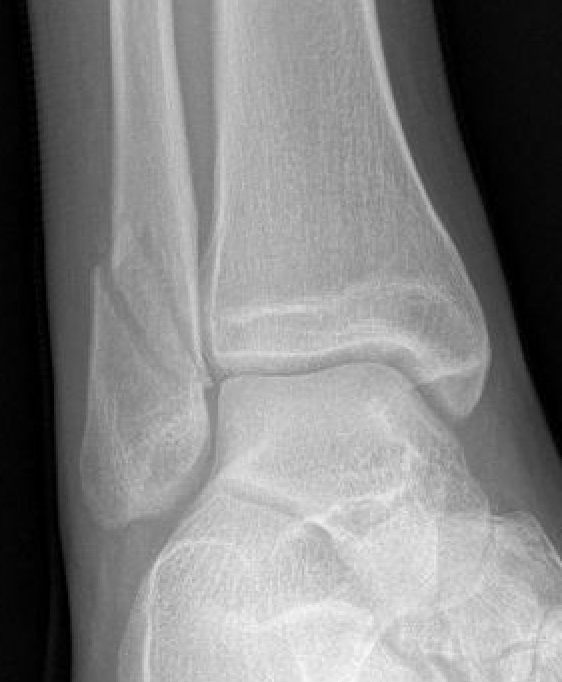

Increased tibio-fibular clear space  Overlap Increased medial clear space

Medial border of the fibula

Lateral border of the posterior tibia (incisura fibularis)

Measured 1 cm above the plafond

Overlap of the fibula and the anterior tibial tubercle

Medial talus to lateral medial malleolus

<5mm AP and mortise

> 6 mm AP view

> 1 mm mortise view

< 4mm

Equal to superior clear space

Syndesmotic injury Syndesmotic injury

Deltoid ligament injury

Lateral talar shift

Ankle AP Xray Syndesmotic Measurements Ankle Mortice Xray Syndesmotic Measurements Mortise